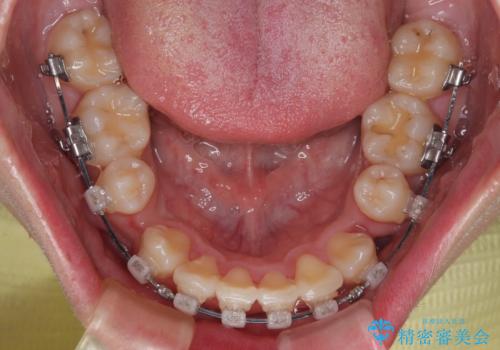

- クリアブラケット

- 1年6ヶ月

特に前歯のデコボコが顕著であり、上下左右第一小臼歯の4本を抜歯し、ワイヤー装置を使用して咬み合わせ高さを改善しながら、歯列を整えて行くこととしました。

移動が順調に進み、1年半の短期間で治療を終えることができました。

前方に突出した上顎前歯の傾斜も改善されました。